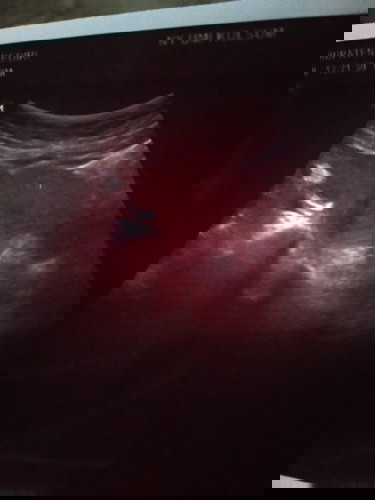

Mau tanya dong bun..ad yg prnah ngalamin kyak sya.sya hamil di usia khamilan 6wek aq kluar flek 2hri.dan sma bidan di suruh usg.aq usg pas udh gk flek lgi.tpi pas usg kta dokternya tidk tumbuh janinya.doktrny tany sma sya udh di tp ap blm.sya jawab udh 2x tp dok dan hsilnya positif.trus dksih obt penguat.susternya di luar bilang ktny hsil usg blm nampak.jdi dsuruh nunggu sbulan.krna sya ingat kta bidan dsuruh tp semingguan lgi.akhirnya sya tp hri ini hsilnya garis 2 bun..gmn solusinya bun?#bantusharing